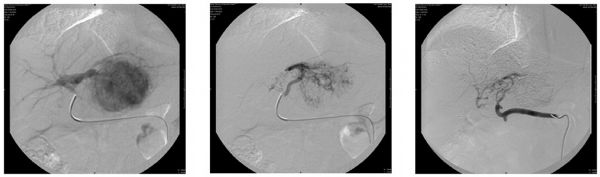

Xi Feng, Madhava Pai, Malkhaz Mizandari, Tinatin Chikovani, Duncan Spalding, Long Jiao, Nagy Habib

Hepatocellular carcinoma (HCC) is the fifth most common neoplasm in the world, closely correlated with viral hepatitis and liver cirrhosis. The vast majority of HCC patients present at a late stage and are unsuitable for surgery due to limited liver functional reserve. Tumors can involve major vessels or hilar structures, necessitating major liver resection and/or rendering liver resection unfeasible. A series of new technologies have been developed to optimise HCC management. Stem cell therapy improves impaired liver functional reserve prior to liver resection. Intravascular radiofrequency ablation recanalises the portal vein invaded by tumour thrombus and endobiliary radiofrequency ablation restores and extends biliary patency of the bile duct invaded by malignancy. Laparoscopic radiofrequency assisted liver resection minimizes blood loss and avoids liver warm ischemia, while increasing parenchymal sparing. These benefits combined maximize the safety of liver resection.